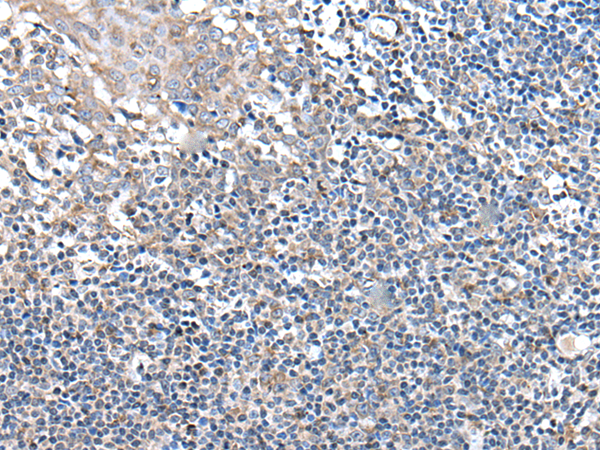

分类: 科研抗体货号: P12899别名: IGI; IGVPB; VPREB; CD179a应用: IHC反应种属: Human